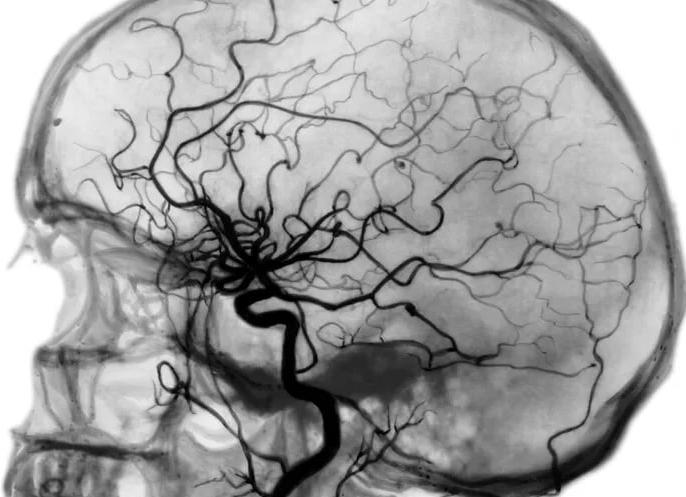

Церебральная ангиография сосудов головного мозга

На современном этапе развития медицины существуют дорогие и дешёвые, инвазивные и неинвазивные исследования. Церебральная ангиография представляет собой рентгенологический метод визуализации сосудов головного мозга с помощью введения контрастного вещества в сосудистое русло.

Для исследования состояния сосудов головного мозга и черепа используется современный метод — церебральная ангиография. Это рентгенологический инструментальный метод обследования, суть которого заключается во введении в сосудистое русло головного мозга контрастного вещества с последующим выполнением рентгенографии.

Благодаря контрастному веществу на снимке получается сосудистый рисунок в виде слепка, на котором видны изменения стенок, места сужения просвета артерий или наличия преграды для кровотока, аномалии и выпячивания стенок. Данное исследование является инвазивным, то есть таким, при котором выполняется операция пункции (прокола) сосуда черепа, с последующим введением в него контрастного вещества.

Ангиография сосудов головного мозга (церебральная ангиография или ангиография церебральных сосудов) назначается для оценки состояния сосудов головного мозга и исследования мозгового кровообращения. Диагностика проводится с помощью рентгеновского аппарата или специального томографа.

При ангиографии в сосуд вводится специальное контрастное вещество и параллельно проводится рентгенологическое исследование – это может быть классическая рентгенография, КТ или МТ-томография. Данная методика предоставляет возможность последовательно изучить все фазы кровотока в головном мозге (прохождение крови через крупные артерии, мелкие сосуды и вены) и установить локализацию патологических изменений в его кровеносной системе.